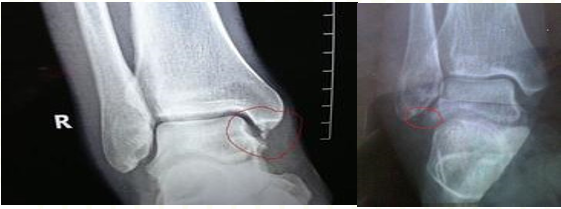

旋后扭伤分类

依据韧带损伤程度(美国医学会分类),分为如下三类:

Ⅰ级:韧带过度拉伸;

Ⅱ级:部分韧带撕裂;

Ⅲ级:韧带完全撕裂。

外旋位扭伤受伤时距骨受到外旋外力,或小腿内旋距骨受到相对外旋外力。随着外旋暴力增大下胫腓联合主要韧带断裂,下胫腓联合分离。严重的多合并外踝骨折或内侧韧带断裂。

3级:韧带完全断裂,存在明显的肿胀和疼痛,关节不稳定。建议“U”型石膏轻度“矫枉过正”固定,撕脱骨折可同法处理。